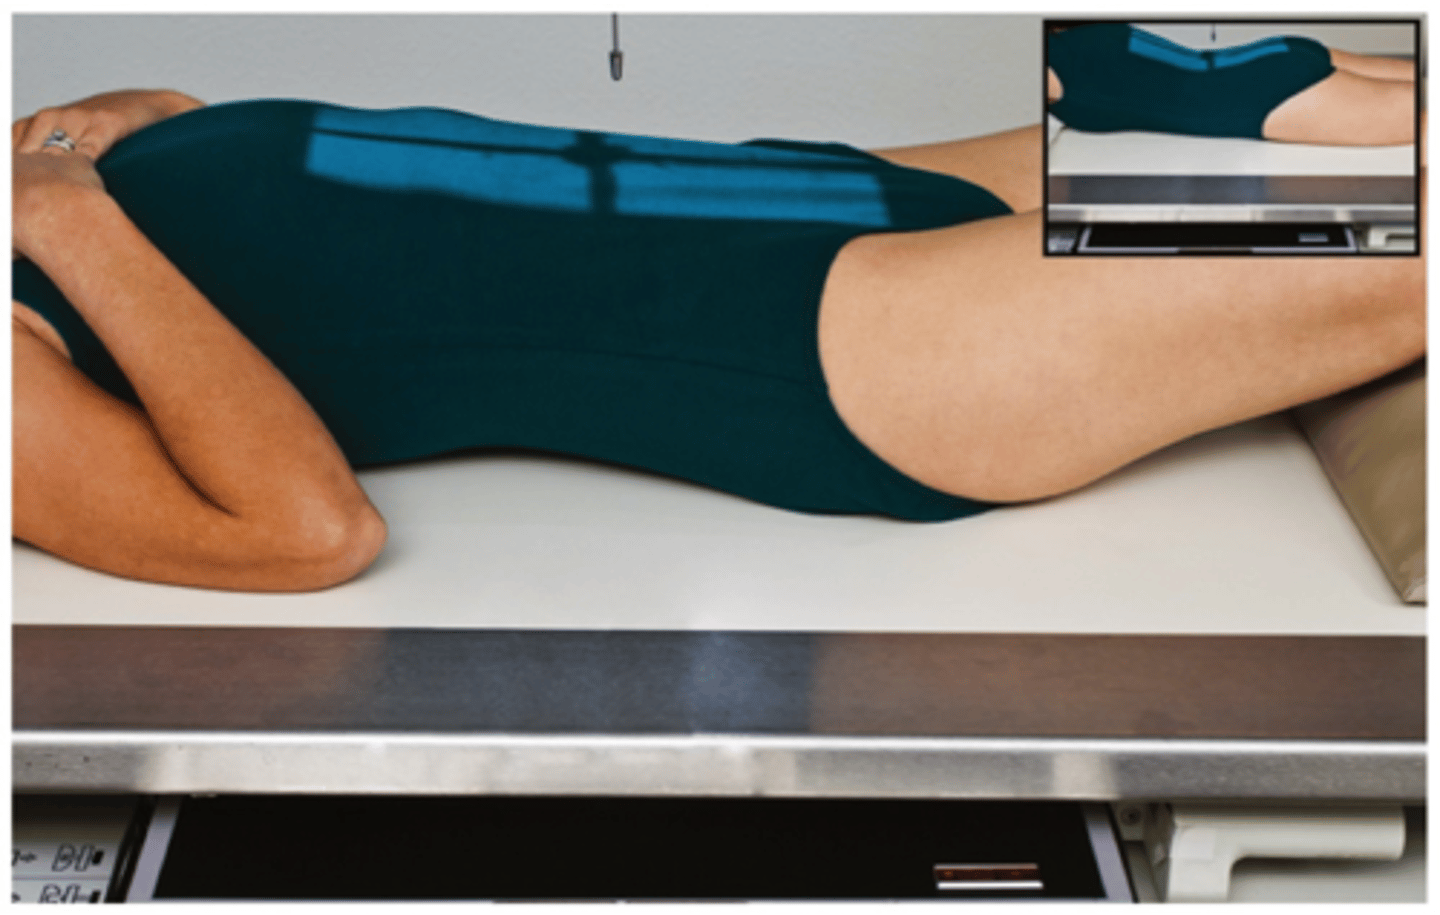

Go through the STAMPSBC list for the Oblique lumbar spine

S - no shielding

T - 40 mAs @ 80 kVp

A - no angle

M - marker on cassette in light field

P - supine w/ 45 degree rotation

S - 40

B - expiration

C - 14 x 17 lengthwise

Where do you center for Oblique L-spine?

at the crest & 2" in from upside ASIS

PO Oblique L-spine demonstrate which zygapophyseal joint?

downside

AO Oblique L-spine demonstrates which zygapophyseal joint?

upside